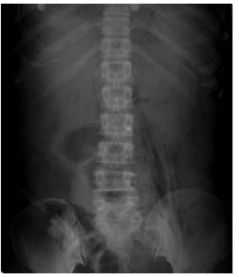

181. 56 歲糖尿病病人,一週前出現下背痛及發燒的症狀,他院診斷為敗血症合 併酮酸中毒,因意識改變而轉至本院急診。檢查和檢驗結果發現,白血球 及發炎指數升高,腹部 X 光如圖所示,關於此疾病之敘述,下列何者較不適當? (A)若病人無明顯感染源而產生上述的疾病,稱為原發性病變,多由肺 炎鏈球菌(Streptococcus pneumoniae)引發。 (B)若病人是經由鄰近器官感染後,直接侵犯而引起的,稱為次發性病 變,則是以腸道桿菌為主。 (C)臨床治療,以抗生素及引流為主。 (D)綜合此病人的病史、臨床表現和檢查結果,此病人之細菌培養結 果,最可能為肺炎克雷白氏桿菌(Klebsiella pneumoniae) 。